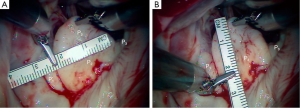

A 63-year-old man presented with symptomatic severe mitral regurgitation. Both trans-esophageal 3-D echocardiography and operative linear measurements showed a 25 mm long A2 anterior leaflet with a very wide (23 mm) prolapsing 30 mm long P2 posterior mid-scallop (Figure 1A,B). P1 and P3 were diminutive in height and width (Figure 2). A ‘haircut’ posterior leaflet-plasty was done to maintain leaflet-annular integrity, shorten and reduce the prolapsing P2 and preserve adequate tissue for coaptation.

Figure 1 shows a mitral valve with a very large, lengthy P2 scallop. Either redundant or ruptured chords result in a large anteriorly directed flow jet. Because of deep indentations on both sides, there is often a P2 ‘independence’, which does not provide adjacent P1 and P3 chordal support. Thus, maximal stress is placed on chords supplying P2. In this instance, a complete P2 resection can create an annular gap that is impossible to close and a small P1 and P3 preclude performing a leaflet sliding-plasty to fill the defect.